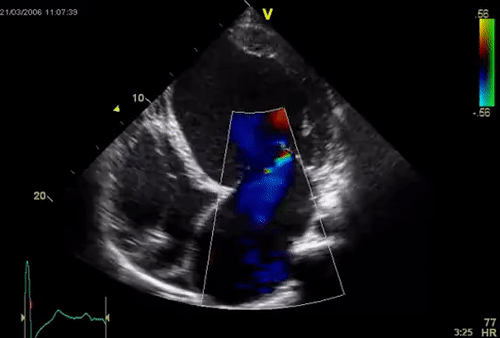

Mitral valve is essentially avascular structure, Still, ischemia affects this valve not by valve necrosis but by other sub valvular mechanisms .Note the MR here is due to poor motion of PML due to ischemic LV dysfunction.